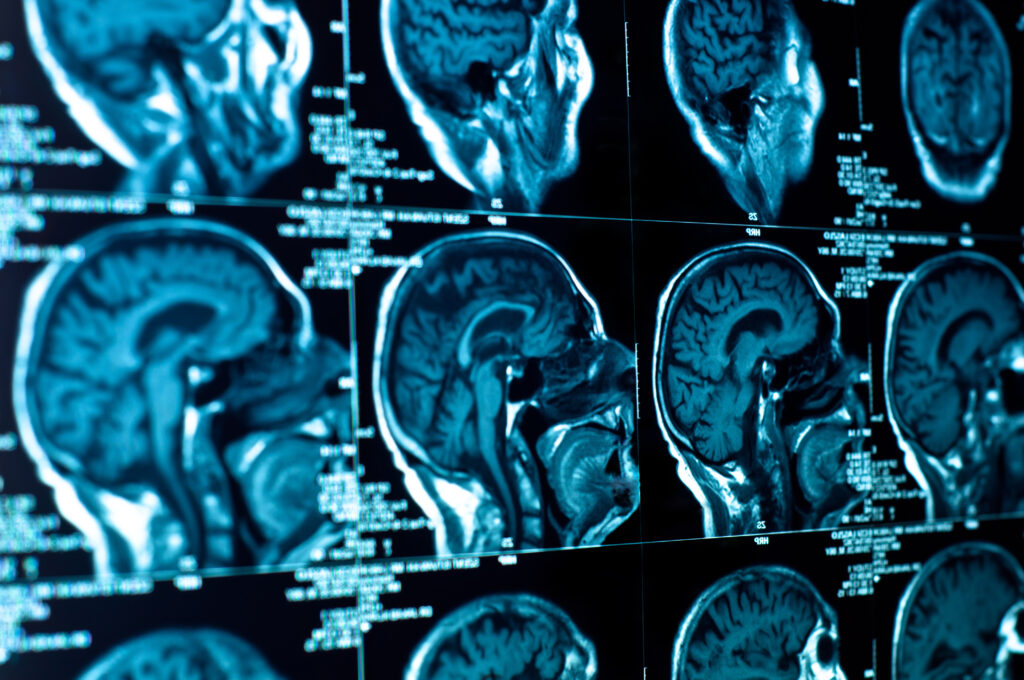

Researchers have identified five major stages of human brain development, revealing that the brain does not reach its full “adult mode” until the early 30s.

The study, based on brain scans from nearly 4,000 people aged from infancy to 90, uncovered four major turning points in brain organisation occurring at approximately ages 9, 32, 66 and 83. These shifts divide life into five broad developmental “epochs” marked by distinct changes in neural wiring.